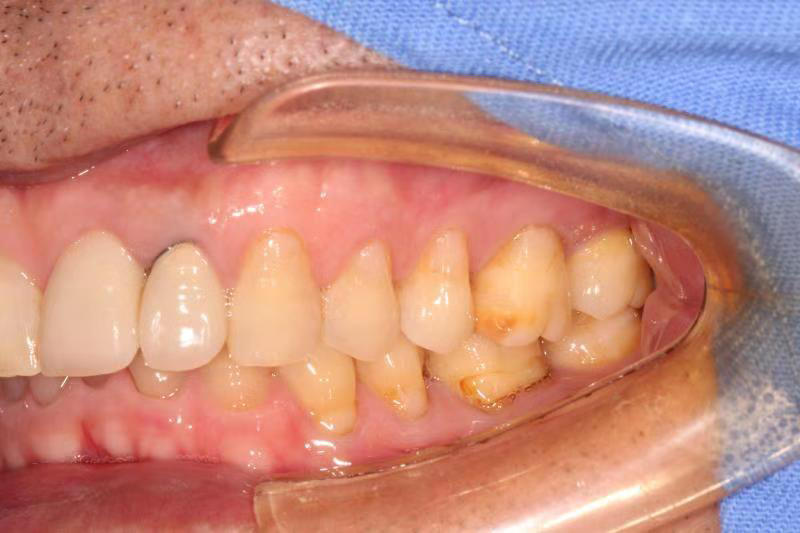

患者中年男性,左上中切牙外院烤瓷冠修复多年,因牙冠脱落前来就诊,由于牙冠制作不够密合,牙齿已经腐烂成残根,无法修复,只能进行种植修复,由于是门牙,我们在做完种植术后为患者制作了临时冠,最大程度保证了美观性。